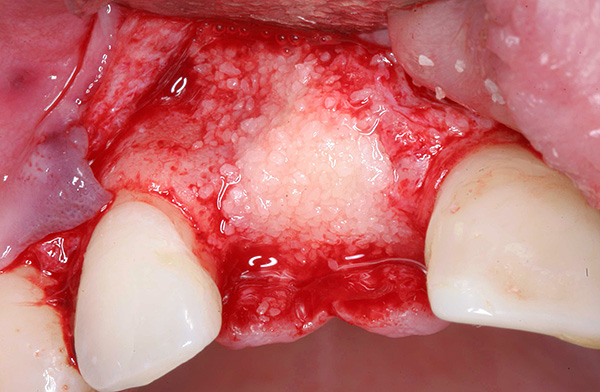

A foto abaixo mostra um exemplo de extensão do tecido ósseo antes da implantação do dente:

Após a remoção do implante móvel, é realizada uma preparação complexa do poço para a próxima implantação, que pode ser realizada após 1-2 meses. Por exemplo, com uma diminuição significativa no tecido ósseo ou na proximidade do seio maxilar, pode ser necessário construir o osso da mandíbula sob o implante dentário (operação de elevação do seio).